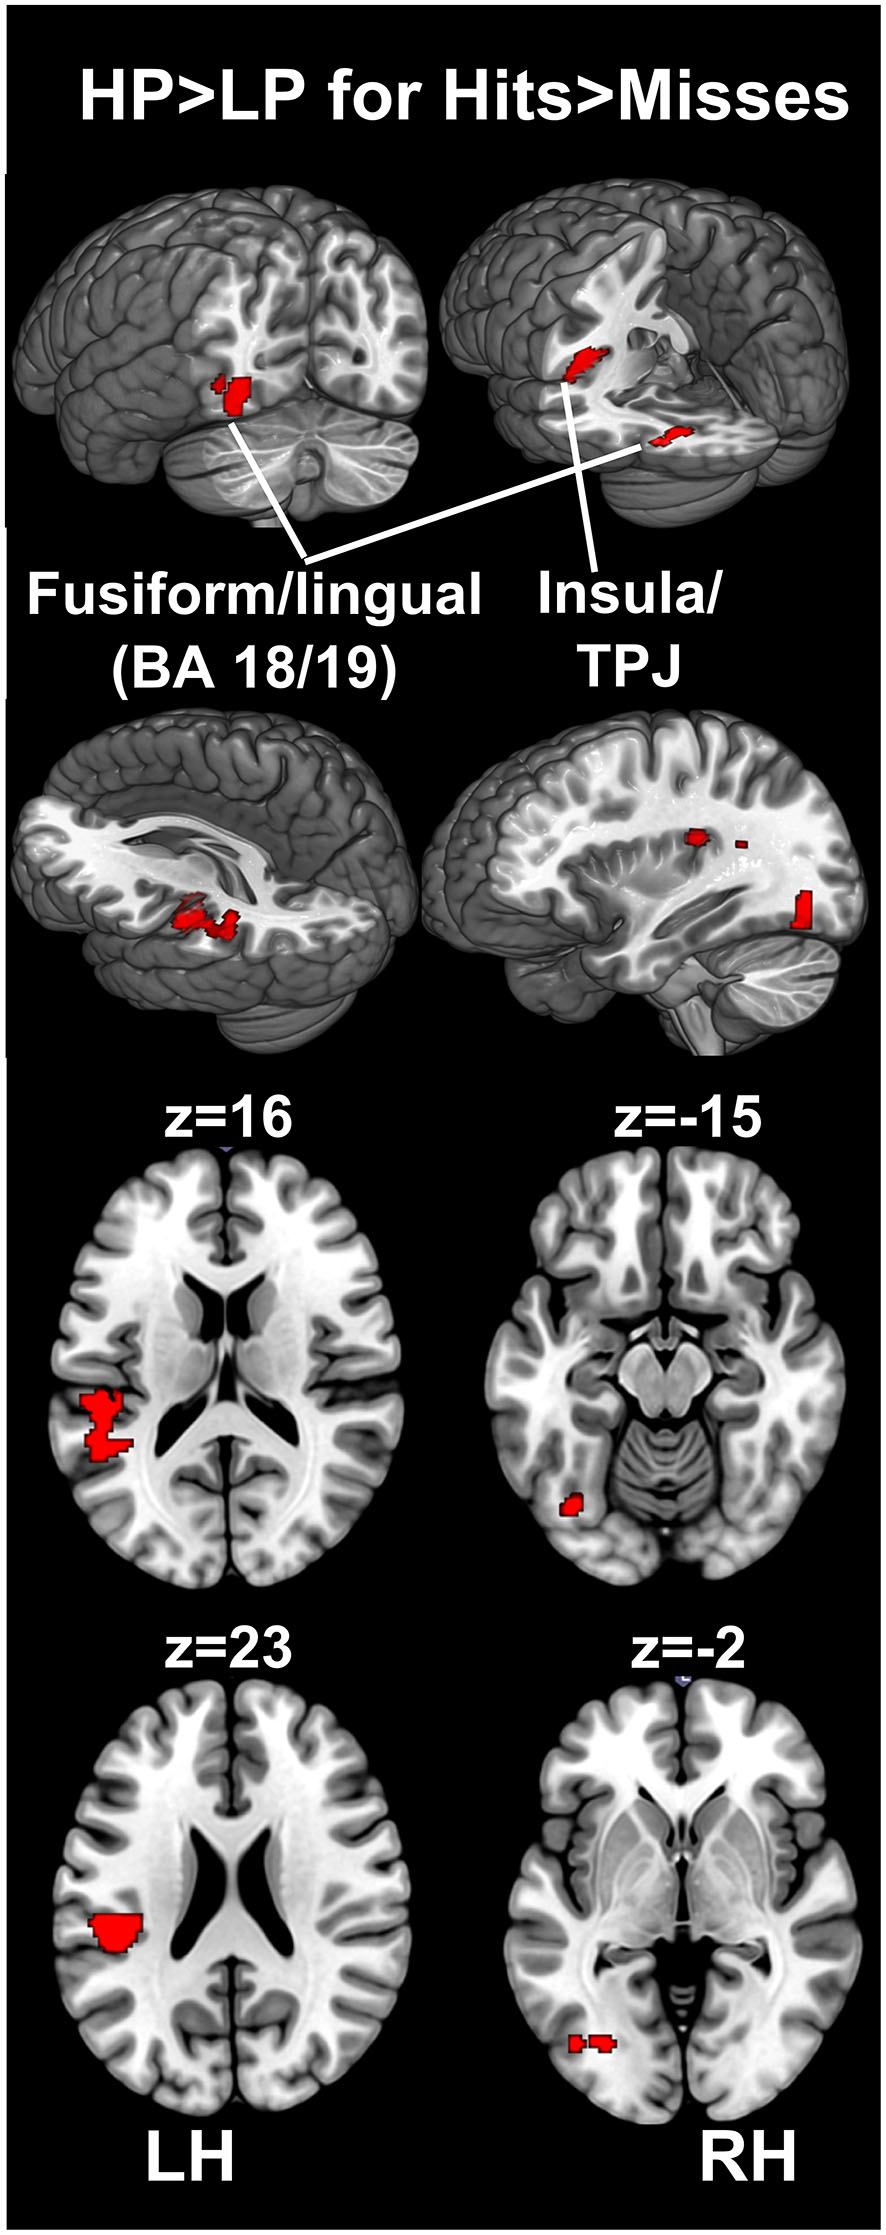

For the encoding of mnemonic material later remembered, our analysis resulted in activations present in two cortical regions, namely the insula/temporo-parietal junction (TPJ) and the FFG of the left hemisphere. This analysis revealed an interaction between post-experimental group assignment and recognition performance, or in other words increased activation for the HP group compared to the LP group, for the contrast hits > misses in two activation clusters. The insula/TPJ cluster covered both Brodmann Area (BA) 13 and BA 40, and was located at the posterior part of the insula, covering also ventral aspects of the TPJ. The FFG cluster comprised both BA 18 and BA 19 and covered mainly the more dorsally located FFG, but also small parts of the more ventrally located lingual gyrus. A detailed summary of the activated clusters, including peak coordinates, T values, cluster sizes, and effects sizes (Cohen’s d; Cohen, 1988) can be found in Table 2 and the results are visualized in Figure 3. As can be seen from the parameter estimates presented in Figure 4, HP showed higher activity both in the FFG and in the insula/TPJ for hits as compared to misses. Importantly, HP also showed more activity for hits than the LP participants in both clusters. The reverse contrast, LP > HP for hits > misses did not reveal significant activation.

Figure 3

fMRI results. The figure illustrates differences between the HP and the LP group for the contrast hits > misses. To correct for multiple comparisons, an uncorrected voxel-level threshold of p = 0.001 (t = 3.2) was set, and in combination with a cluster-size threshold of k = 125 voxels resulted in an estimated whole-brain corrected α=5% level. The cluster-size threshold was determined using Monte Carlo simulations (10,000 iterations). Increased activity for the HP group was found in the left FFG, covering both BA 18 and 19, including parts of the fusiform and the lingual gyrus. Furthermore, increased activity for the HP group was found in the left insular cortex. This cluster covered mainly the posterior insula (BA 13) and extended towards the ventral part of the TPJ at BA 40. BA, Brodmann area; FFG, fusiform gyrus; HP, high performers; LH, left hemisphere; LP, low performers; RH, right hemisphere; TPJ, temporo-parietal junction.